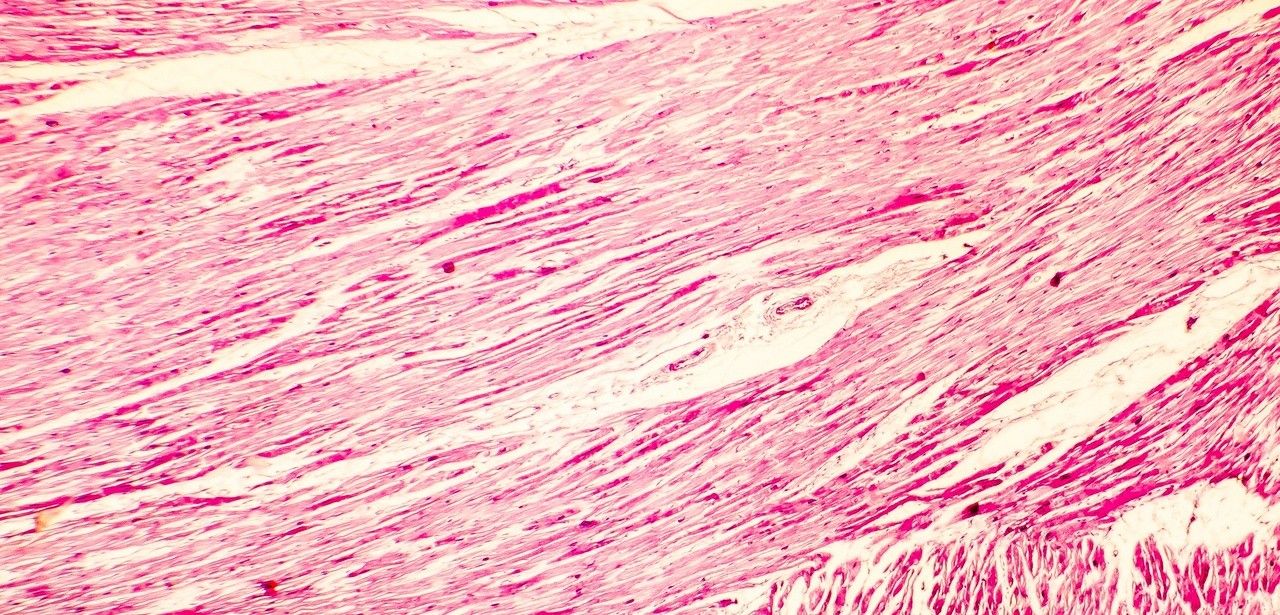

Herzinsuffizienz ist eine chronische Erkrankung, bei der das Herz nicht in der Lage ist, ausreichend Blut durch den Körper zu pumpen, um den Bedürfnissen des Organismus gerecht zu werden. Bei kongestiver Herzinsuffizienz kommt es zu einer Ansammlung von Blut im Gewebe, was zu Symptomen wie Bein- und Knöchelschwellungen führen kann. Weltweit sind etwa 26 Millionen Menschen von dieser Form der Herzinsuffizienz betroffen.